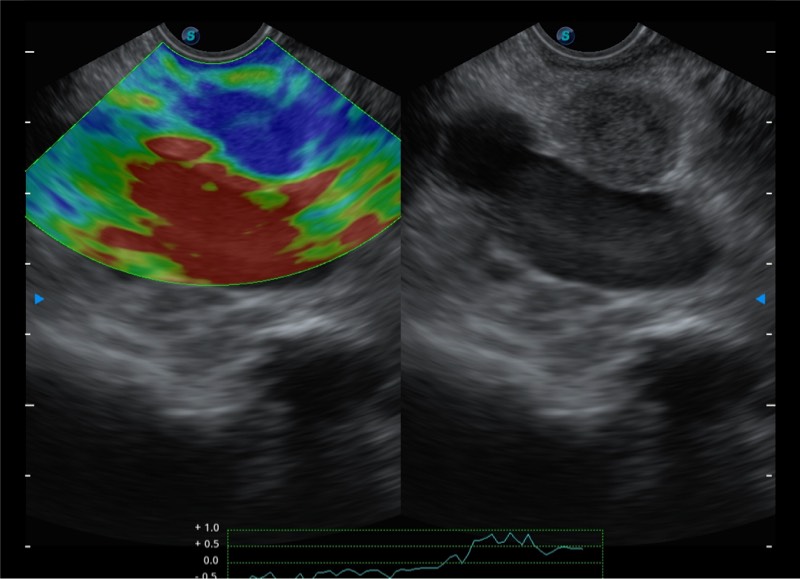

高端超声影像平台

基于二十年的超声技术积累,竞技宝(JJB)官方网站提供了最新一代的独立超声主机,在提供高质量图像的同时满足多学科使用。具备常见多普勒技术并提供弹性成像、声学造影等高端影像技术。新一代传感器具有更强的抗干扰能力并减少图像伪影。